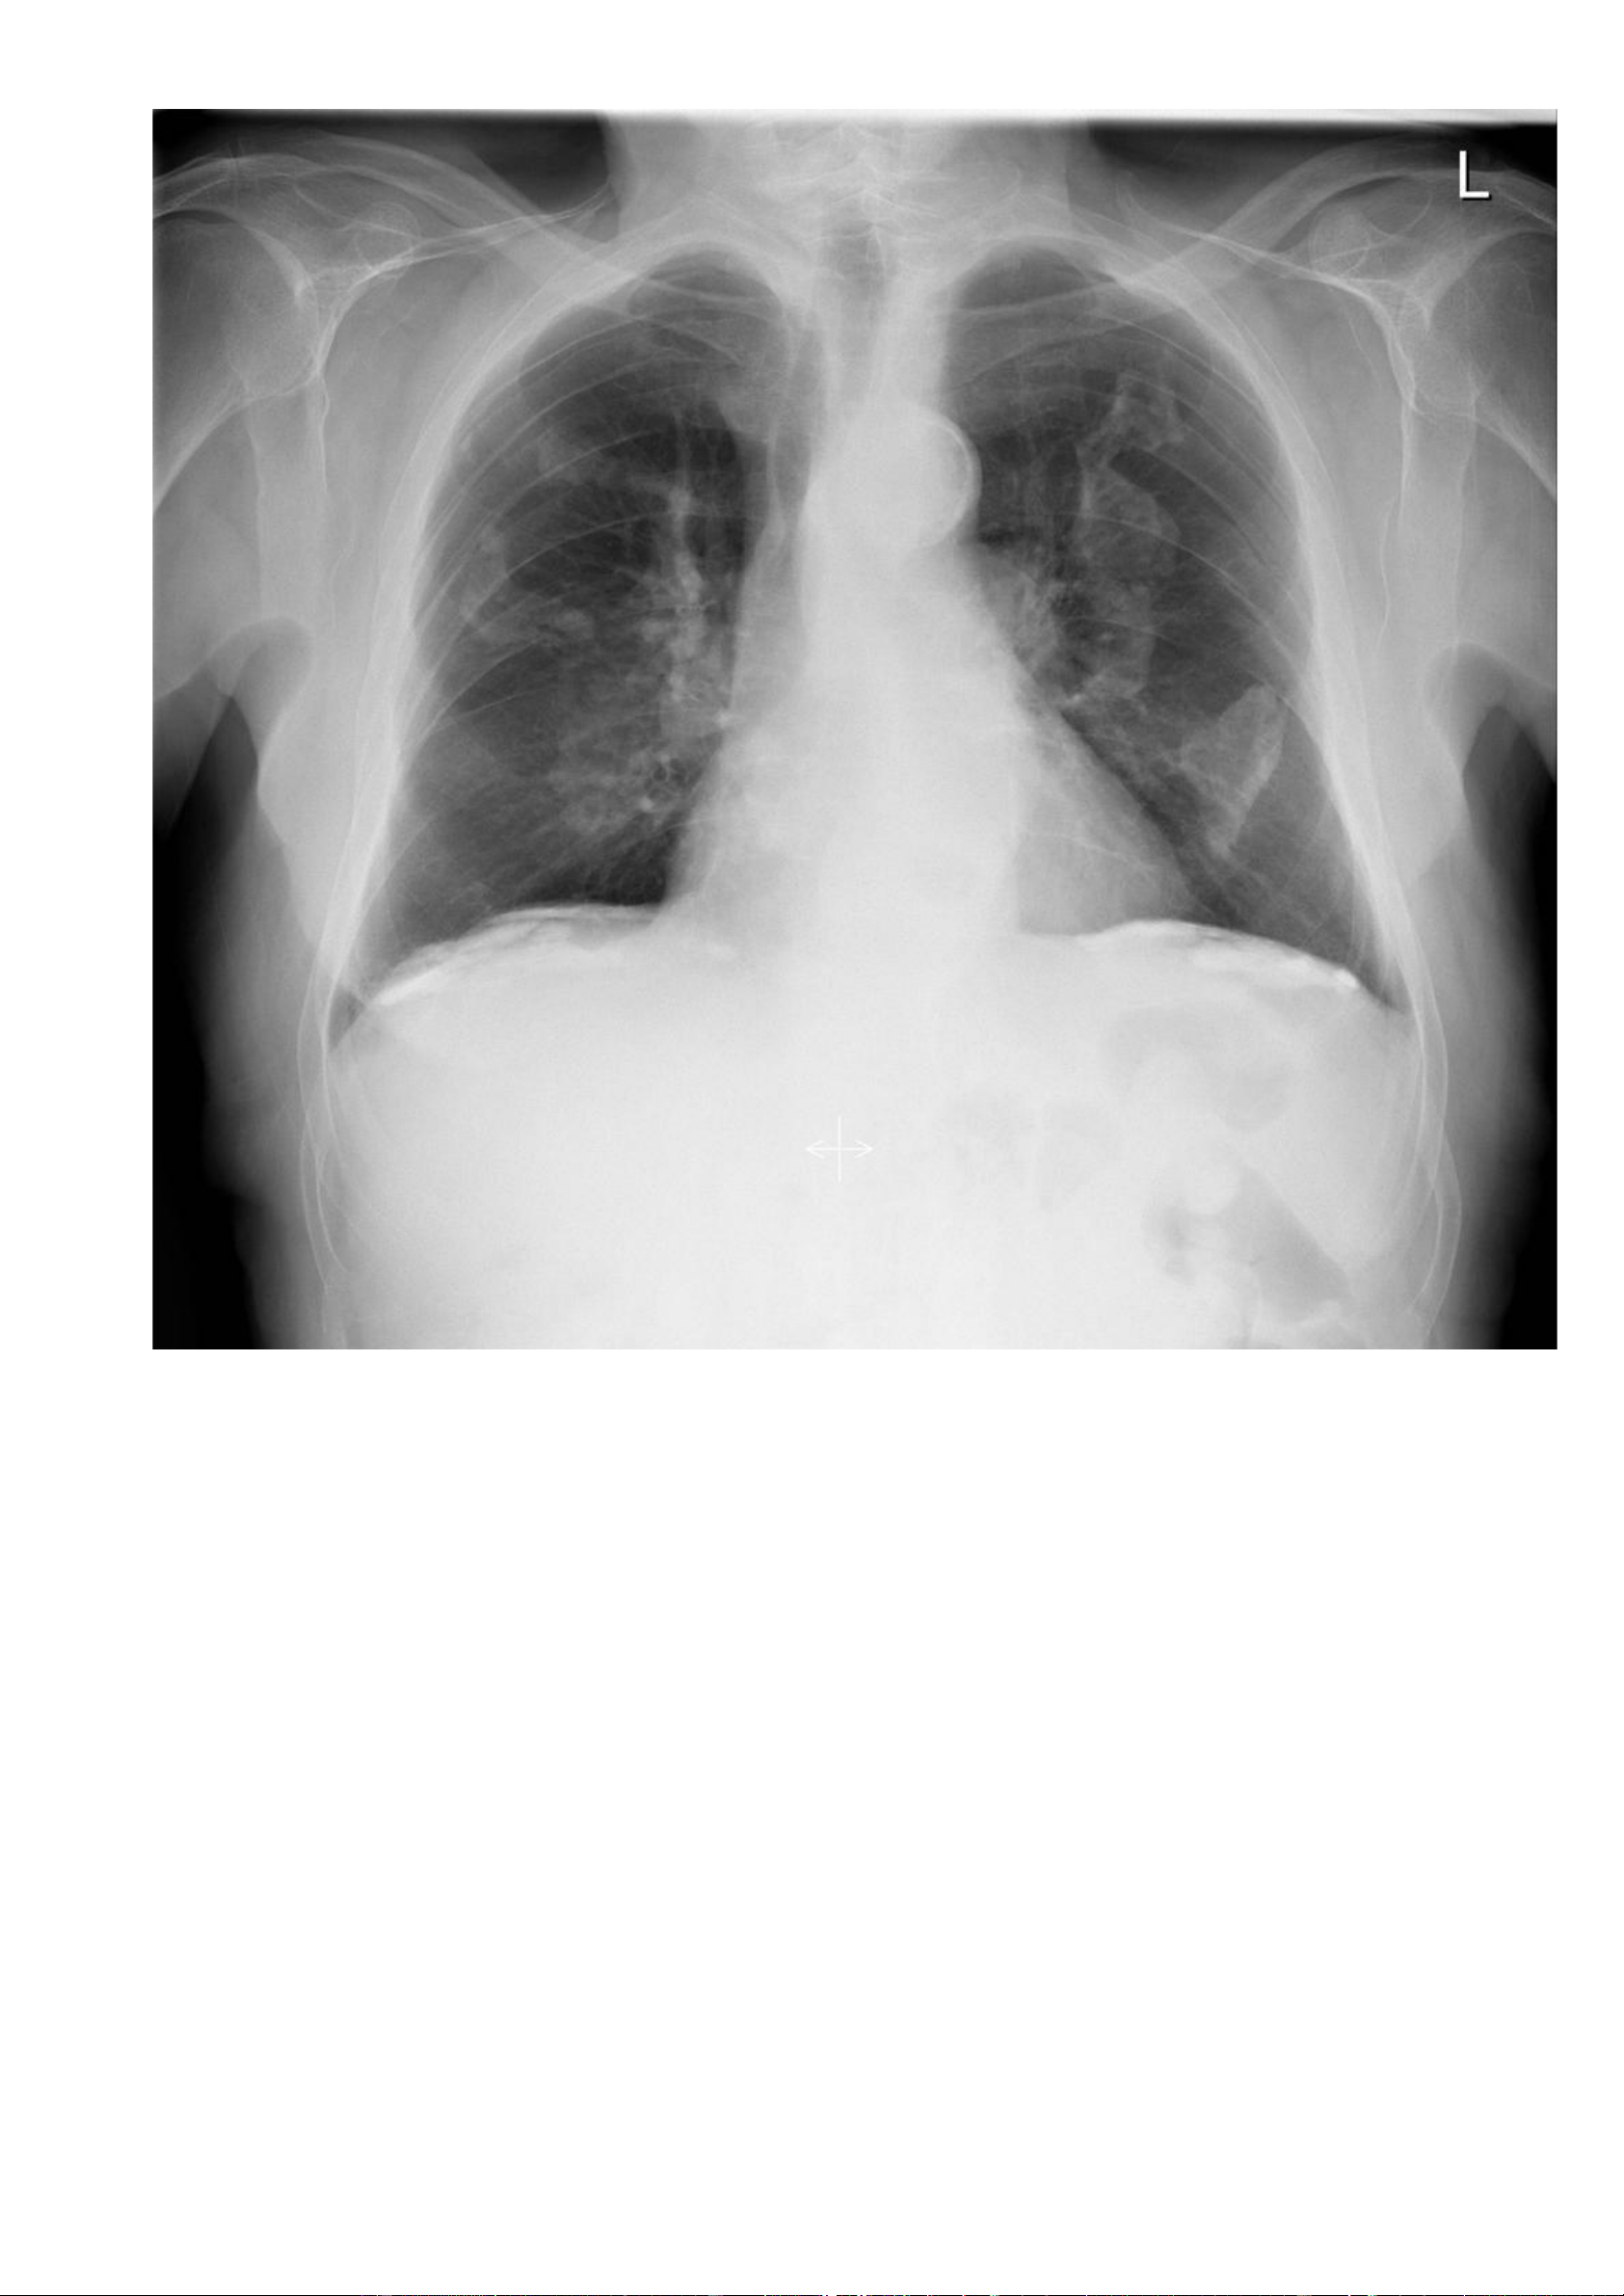

Nguồ https://radiopaedia.org/cases/pleural-plaques -

nh nhân: Bệnh nhân nam, 65 tuổi, khó thở và ho có đờm. - Hình ả lOMoAR cPSD| 22014077 Phan Tùng Bách

Vôi hoá màng phổi hai bên dạng bản đồ, bao gồm cả bề mặt nửa cơ hoành hai bên. lOMoAR cPSD| 22014077 Phan Tùng Bách ờng hợ n link: Thông tin bệ nh X quang: